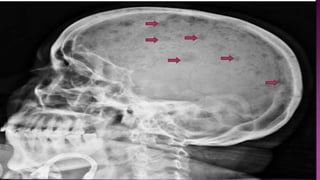

• Lytic lesions – no osteoblastic activity

• Bone lesions – One or more osteolytic lesions ≥5 mm